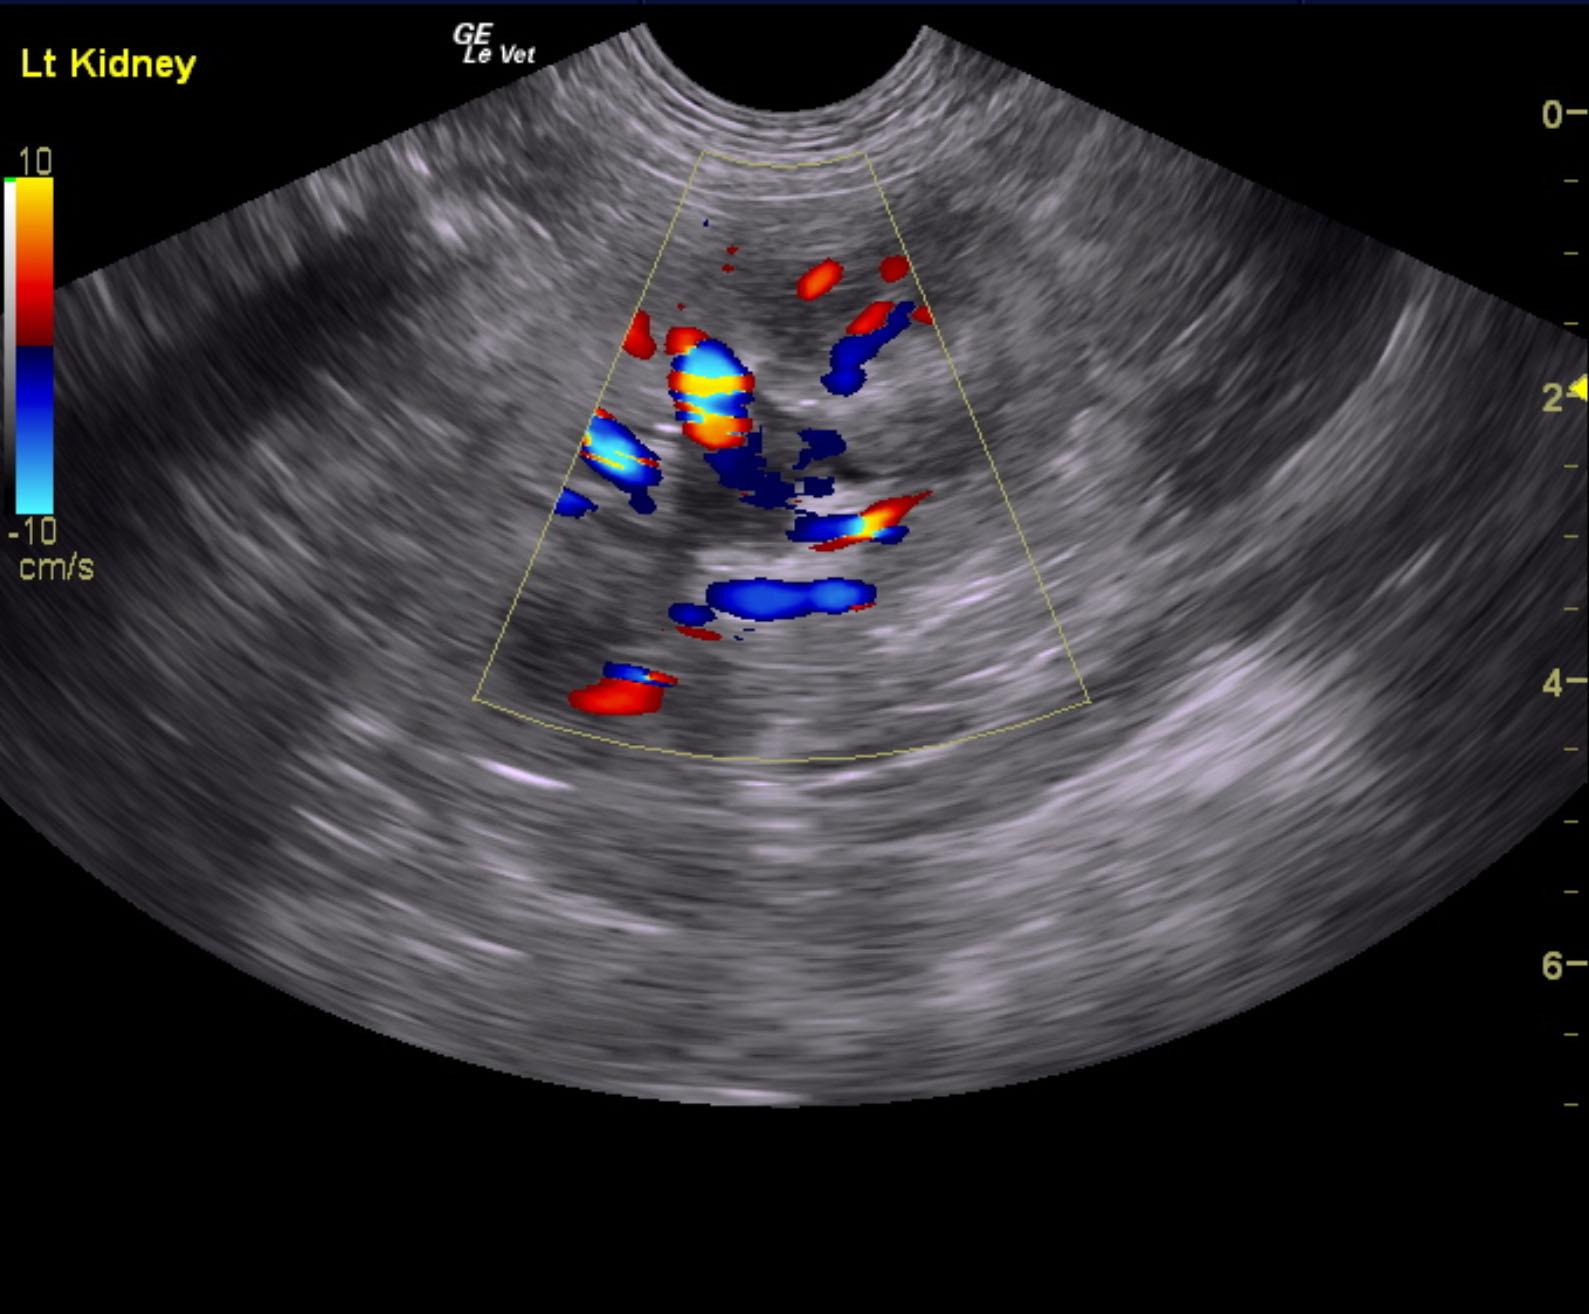

A 5-years-old male neutered Shih Tzu was presented for evaluation of urethral obstruction that had been managed with catheterization. Urinalysis showed SG of 1.008 and proteinuria. Abnormalities on CBC and serum biochemistry were neutrophilia and monocytosis, elevated phosphorus, and azotemia; the latter had improved after being catheterized.